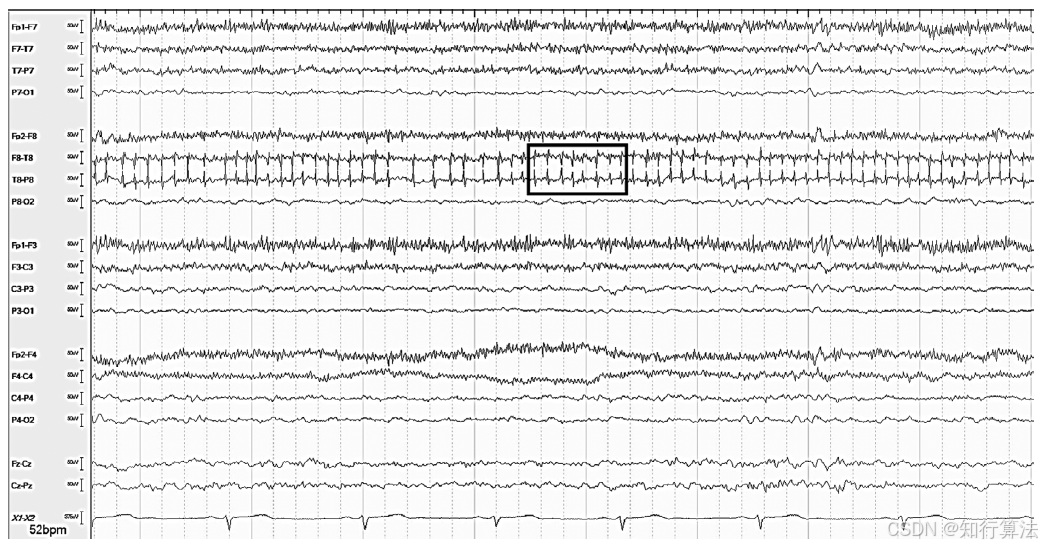

图1:T8 导联尖波样周期性电极伪差

图2:P7 电极处有“爆裂”伪迹。另外请注意心率不齐。